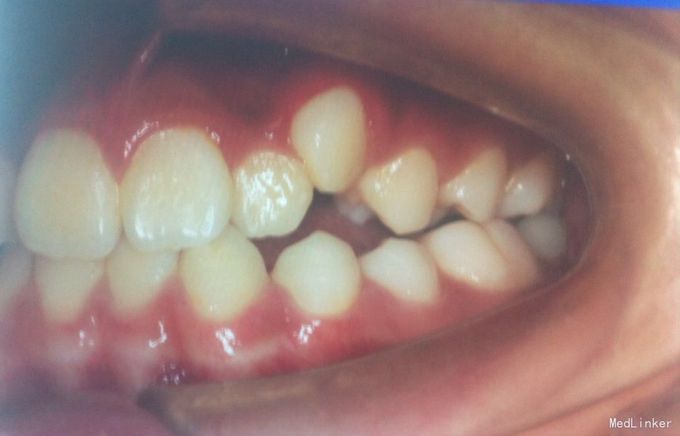

检查:恒牙期 右侧磨牙远中关系,左侧磨牙中性关系 前牙一度深覆合,正常覆盖 32、42未见 13、23唇侧错位 张口型异常 中线左偏约2mm 口腔卫生一般 X线未见32、42牙胚,28、38、48牙胚存在

诊断:安氏三类,先天缺牙 处理:拔牙矫治,直丝弓矫治器,拔除15、25,排齐整平上下牙列,关闭拔牙间隙,矫治后磨牙中性关系,前牙覆合覆盖正常,维持现有面型。